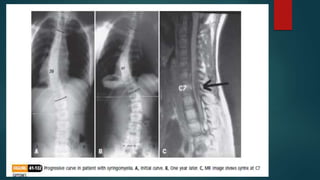

 CRANKSHAFT PHENOMENON:

 With a solid posterior fusion, continued

anterior growth of the vertebral bodies

causes the vertebral body and discs to

bulge laterally toward the convexity and to

pivot on the posterior fusion, causing loss

of correction, increase in vertebral rotation,

and recurrence of the rib hump.